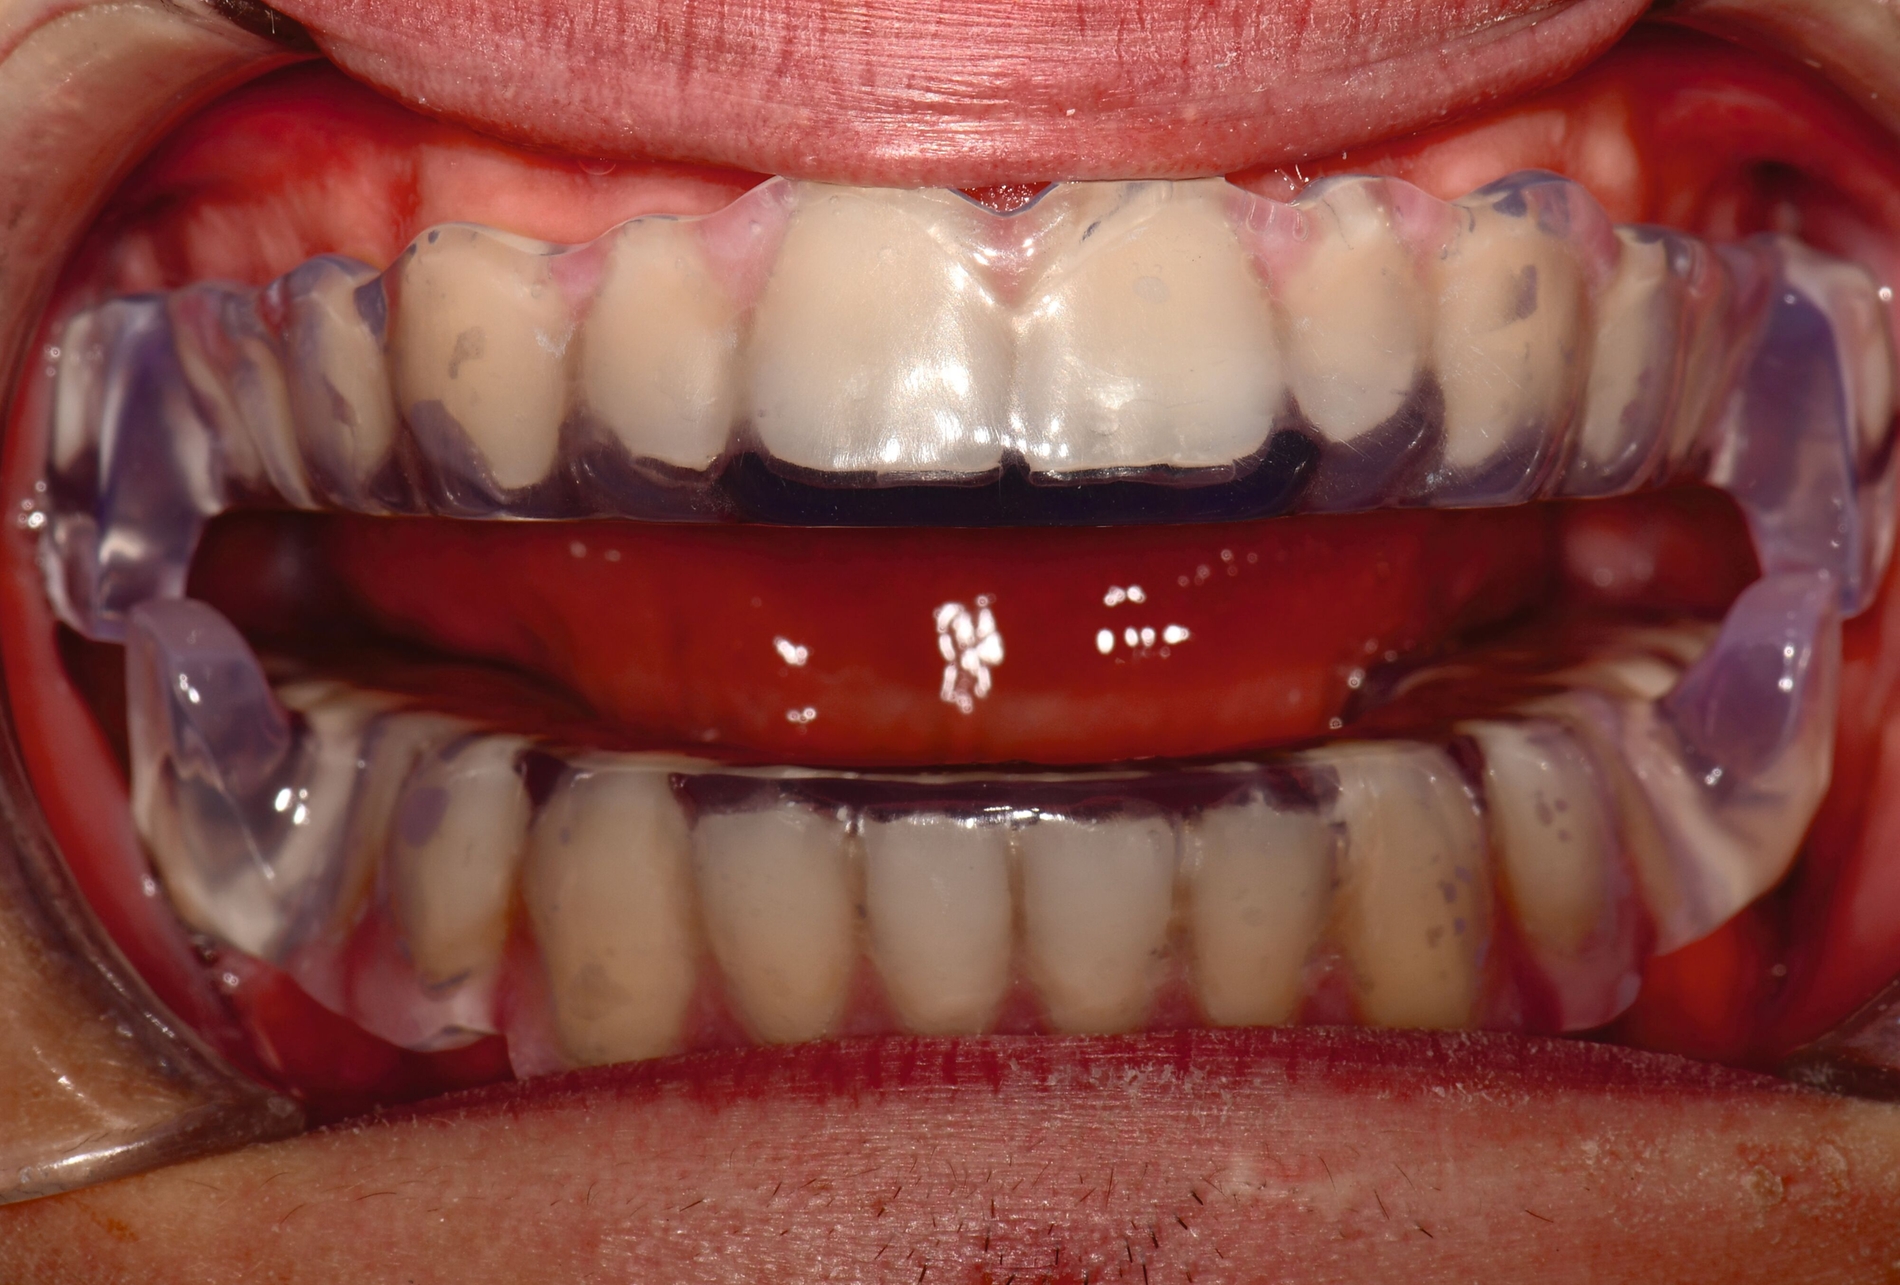

Aligner

Unter den digital gefertigten kieferorthopädischen Apparaturen sind Aligner wohl das bekannteste Beispiel [Ercoli et al., 2014, Robertson et al., 2020]. Die Herstellung von Alignern selbst basiert(e) jedoch auf einer manuellen Fertigung anhand 3-D-gedruckter Modelle und stellt(e) somit bisher eher eine partiell automatisierte Fertigung dar. Die neuesten Entwicklungen erlauben mittlerweile eine Fertigung im direkten 3-D-Druckverfahren [Tartaglia et al., 2021], so dass mühsame, zeitaufwendige Zwischenschritte der manuellen Fertigung entfallen (Abbildung 1a). Weiter profitieren die Patienten von individuelleren Fertigungsmöglichkeiten, da durch die Umsetzung im 3-D-Druck zusätzliche Elemente einfacher und stabiler in den Aligner inkorporiert werden können (Abbildung 1b).